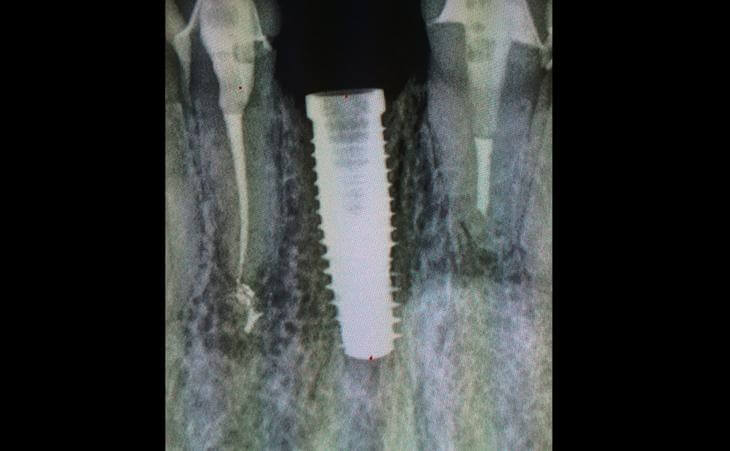

Patient presented with missing lower from tooth. The amount of space available to place an implant was very limited and posed a risk to injure the roots of adjacent teeth. This case was performed under guided surgery to assure perfect placement of the implant without injury to adjacent teeth.